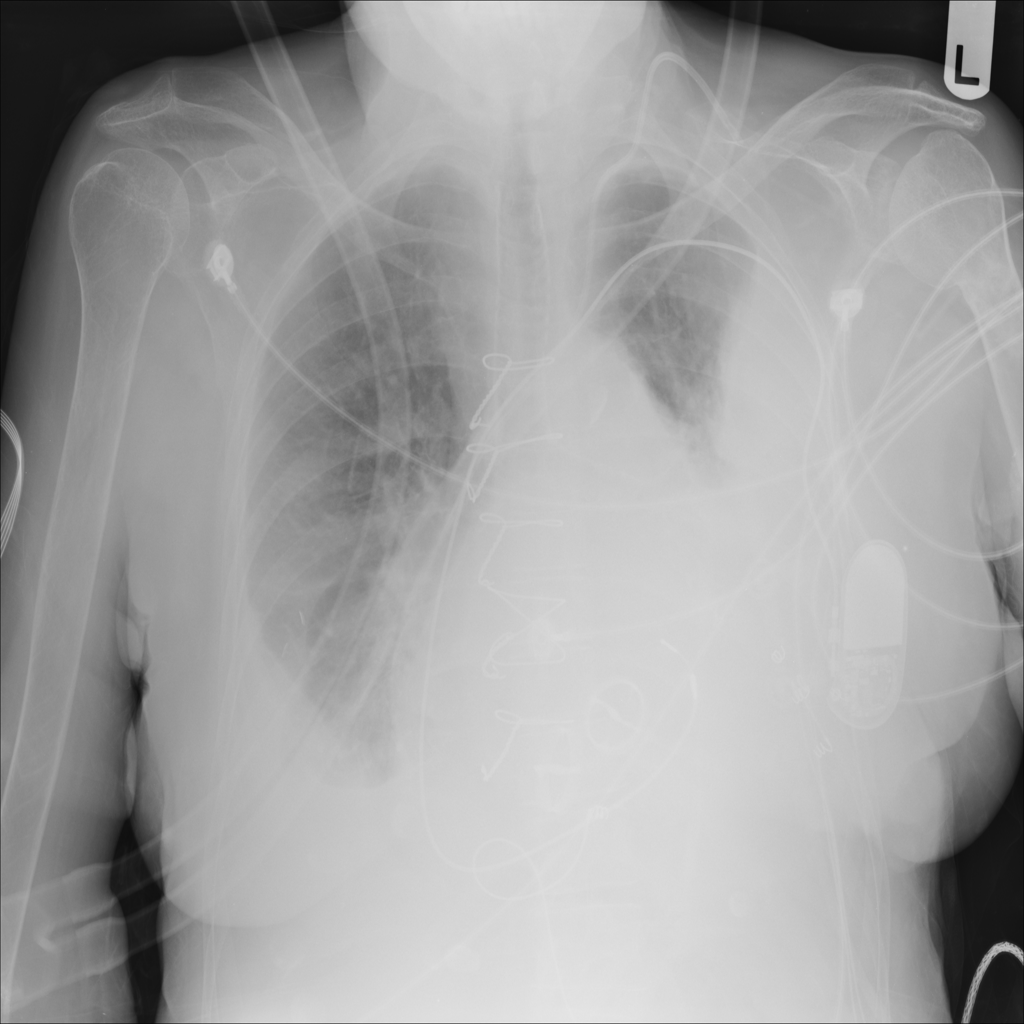

PAT-4639 · IMG-021Effusion

PAT-4639 · IMG-021

PA